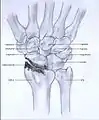

Post-traumatic osteoarthritis can be classified into four stages.[1][7] These stages are similar between SLAC and SNAC wrists. Each stage has a different treatment.

- Stage III: the osteoarthritis is localized in the entire radioscaphoid joint with involvement of the capitolunate joint.

- Stage IV: the osteoarthritis is located in the entire radiocarpal joint and in the intercarpal joints. It also may involve the distal radio-ulnar joint (DRUJ).

Stage III

Stage IV